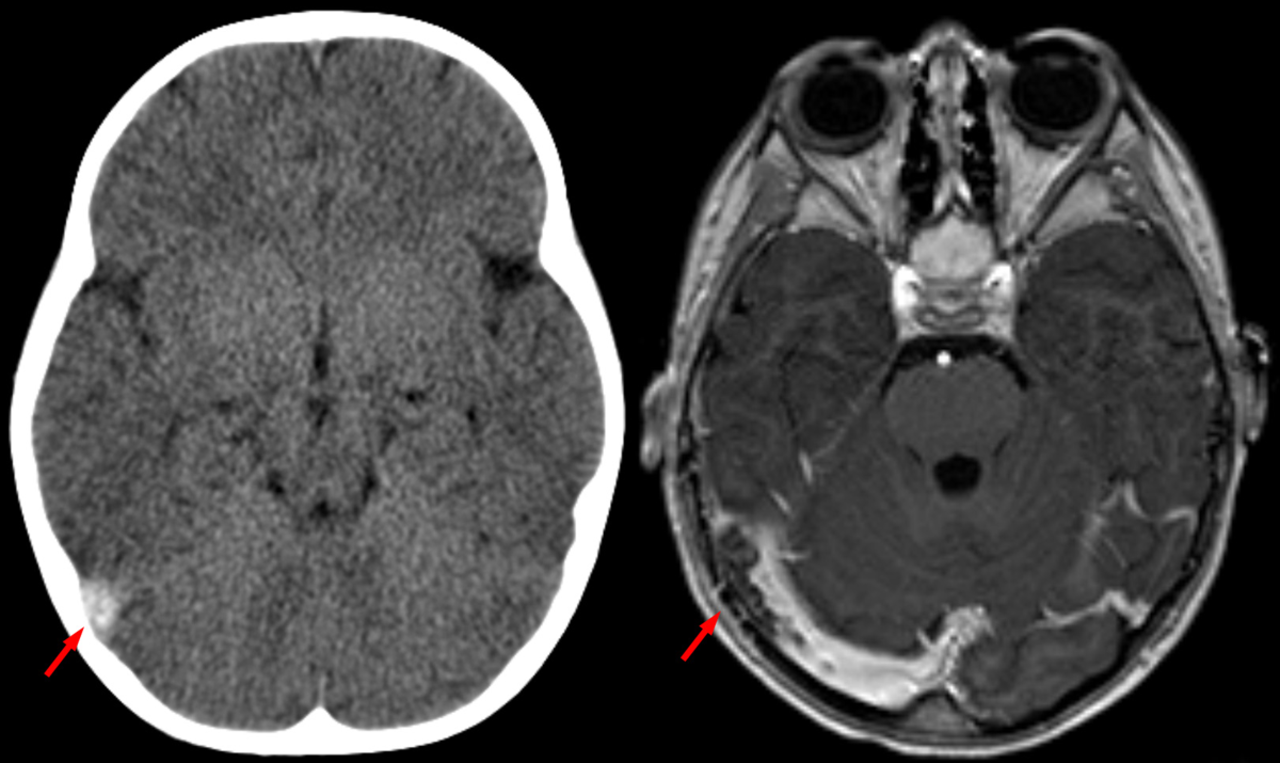

Sinusvenenthrombose in der Computertomographie ohne Kontrastmittel (links) und in der Kernspintomographie T1 mit Kontrastmittel (rechts) beim gleichen Fall. Sinusvenenthrombose in der Computertomographie ohne Kontrastmittel (links) und in der Kernspintomographie T1 mit Kontrastmittel (rechts) beim gleichen Fall. © wikimedia/Hellerhoff (CC BY-SA 3.0)